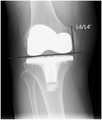

FIG. 4 is a third schematic diagram of a knee joint line using the deep learning-based pre-revision surgery planning method after total knee replacement provided by the present invention;

3. The change of the joint line before and after the revision surgery was measured with the tibial tubercle as a reference point.

In the knee X-ray lateral slice, a tibial plateau tangent l (line connecting the anterior and posterior tibial cortex) is determined, as shown in fig. 4. First, a parallel line l 'passing through the lowest point of femur and tangent to tibial plateau is made, and 1 perpendicular line is made from the protrusion of tibial tubercle to the line l'. The vertical line segment is the joint line, and the length of the vertical line segment is the length of the joint line. The anterior and posterior joint line lengths for revision are designated L6 and L6', respectively. The length of the joint line is L6-L6'. In fig. 4, L6 and L6' are used as examples only, and do not represent that the joint line before and after revision must be the same.

The tibial tubercle is a protrusion protruding forward of the upper end of the tibia, is located below the knee joint, is an attachment point for the patellar ligament, and is an important body surface marker.